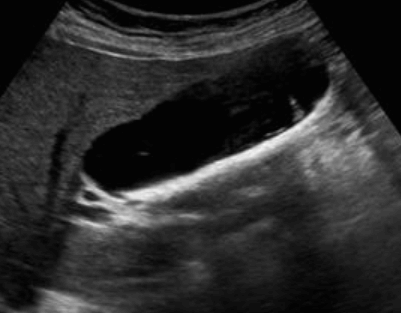

담낭 안에 결석이 존재하는 질환이다. 비정상적인 담즙의 정체와 감염에 의해 담석이 형성된다. 작은 담석은 담낭관의 폐쇄를 초래하므로 담석의 수가 많고 크기가 작을수록 위험하다. 비만(fat), 다산(fertile), 여성 또는 나이가 많을수록 발생 확률이 높다. 증상은 우상복부통증, 오심과 구토 등이 나타난다. 담석의 성분은 cholesterol, calcim bilirubin, calcium carbonate이며 대부분 bilirubin 또는 cholesterol이다.

- 강한 고에코의 반사체 (strong echogenic sign)

- 후방음향음영 (posterior acoustic shadow)

- 환자 체위에 따라 움직임 (rolling stone sign)

- Wall-echo-shadow (WES) triad = double arc shadow sign

- 콜레스테롤 결석은 강하고 선명한 후방음영이 존재한다

- 색소성 결석은 후방음영이 없다 (체위 변화로 용종과의 감별 필요함)

- Color doppler 적용 시 twinkle artifact 가 보인다